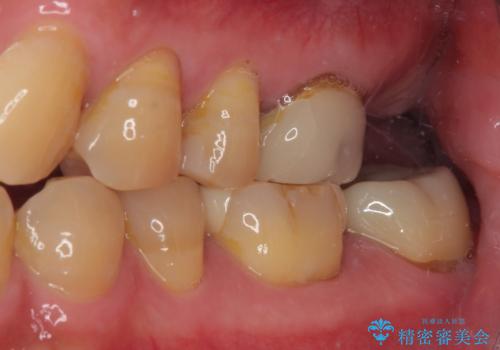

欠損した奥歯 インプラントによる補綴治療

- 破損したクラウンと、奥歯の欠損を気にして来院された患者様です。

奥歯の欠損部はインプラントによる補綴治療を、手前の破損したクラウンは作り替えをご希望でした。

しかしながら、レントゲンやCT画像から、手前の破損したクラウンの根尖部に大きな病変が認められ、インプラント埋入部にまで病変が及んでいることから、まずは手前の根管治療を行い、病変の正体を確認した後にインプラント埋入を行うこととしました。

口があまり開かず、インプラントの埋入角度がやや斜めとなりましたが、機能的には全く問題なく治療を終えることができました。